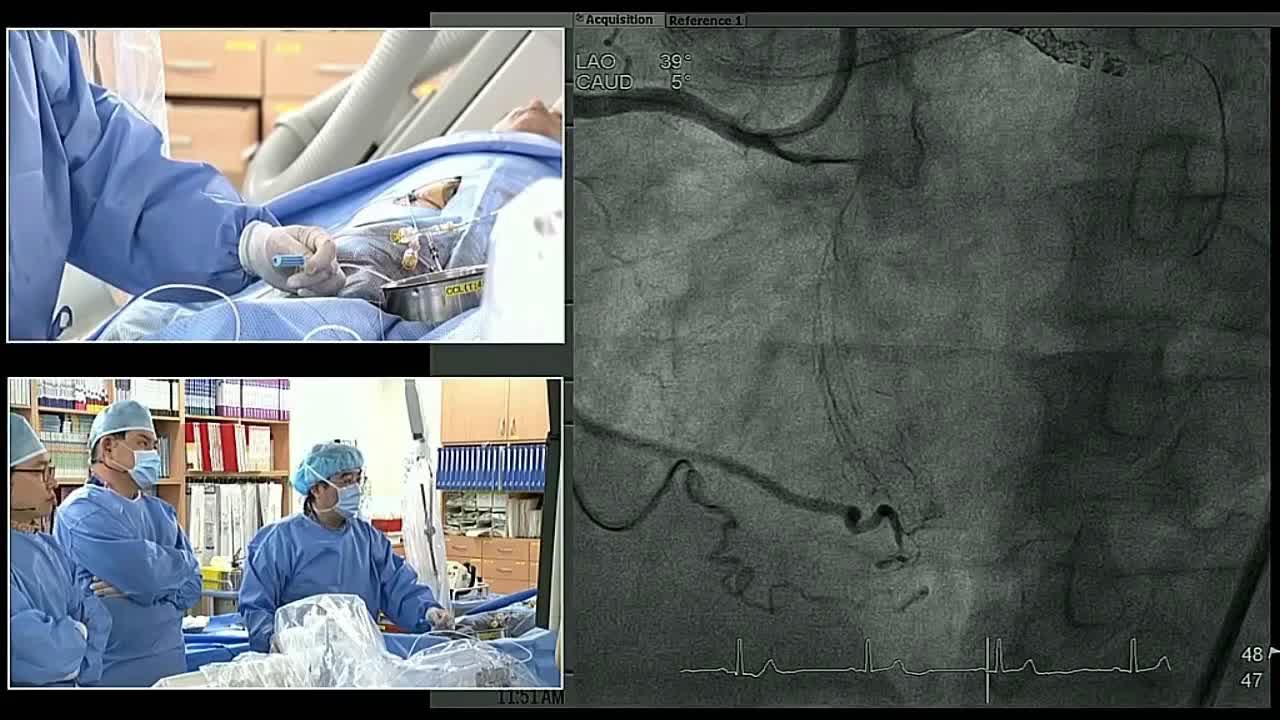

血管内手术现场案例一(4)

血管内手术现场案例一(3)

血管内手术现场案例一(5)

血管内手术现场案例一(6)